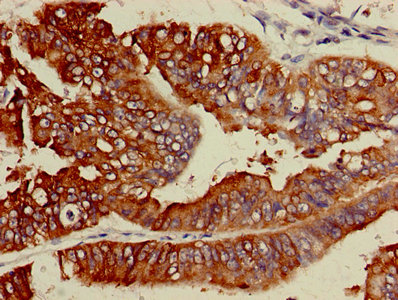

IHC image of CSB-PA891734HA01HU diluted at 1:600 and staining in paraffin-embedded human endometrial cancer performed on a Leica BondTM system. After dewaxing and hydration, antigen retrieval was mediated by high pressure in a citrate buffer (pH 6.0). Section was blocked with 10% normal goat serum 30min at RT. Then primary antibody (1% BSA) was incubated at 4°C overnight. The primary is detected by a biotinylated secondary antibody and visualized using an HRP conjugated SP system.